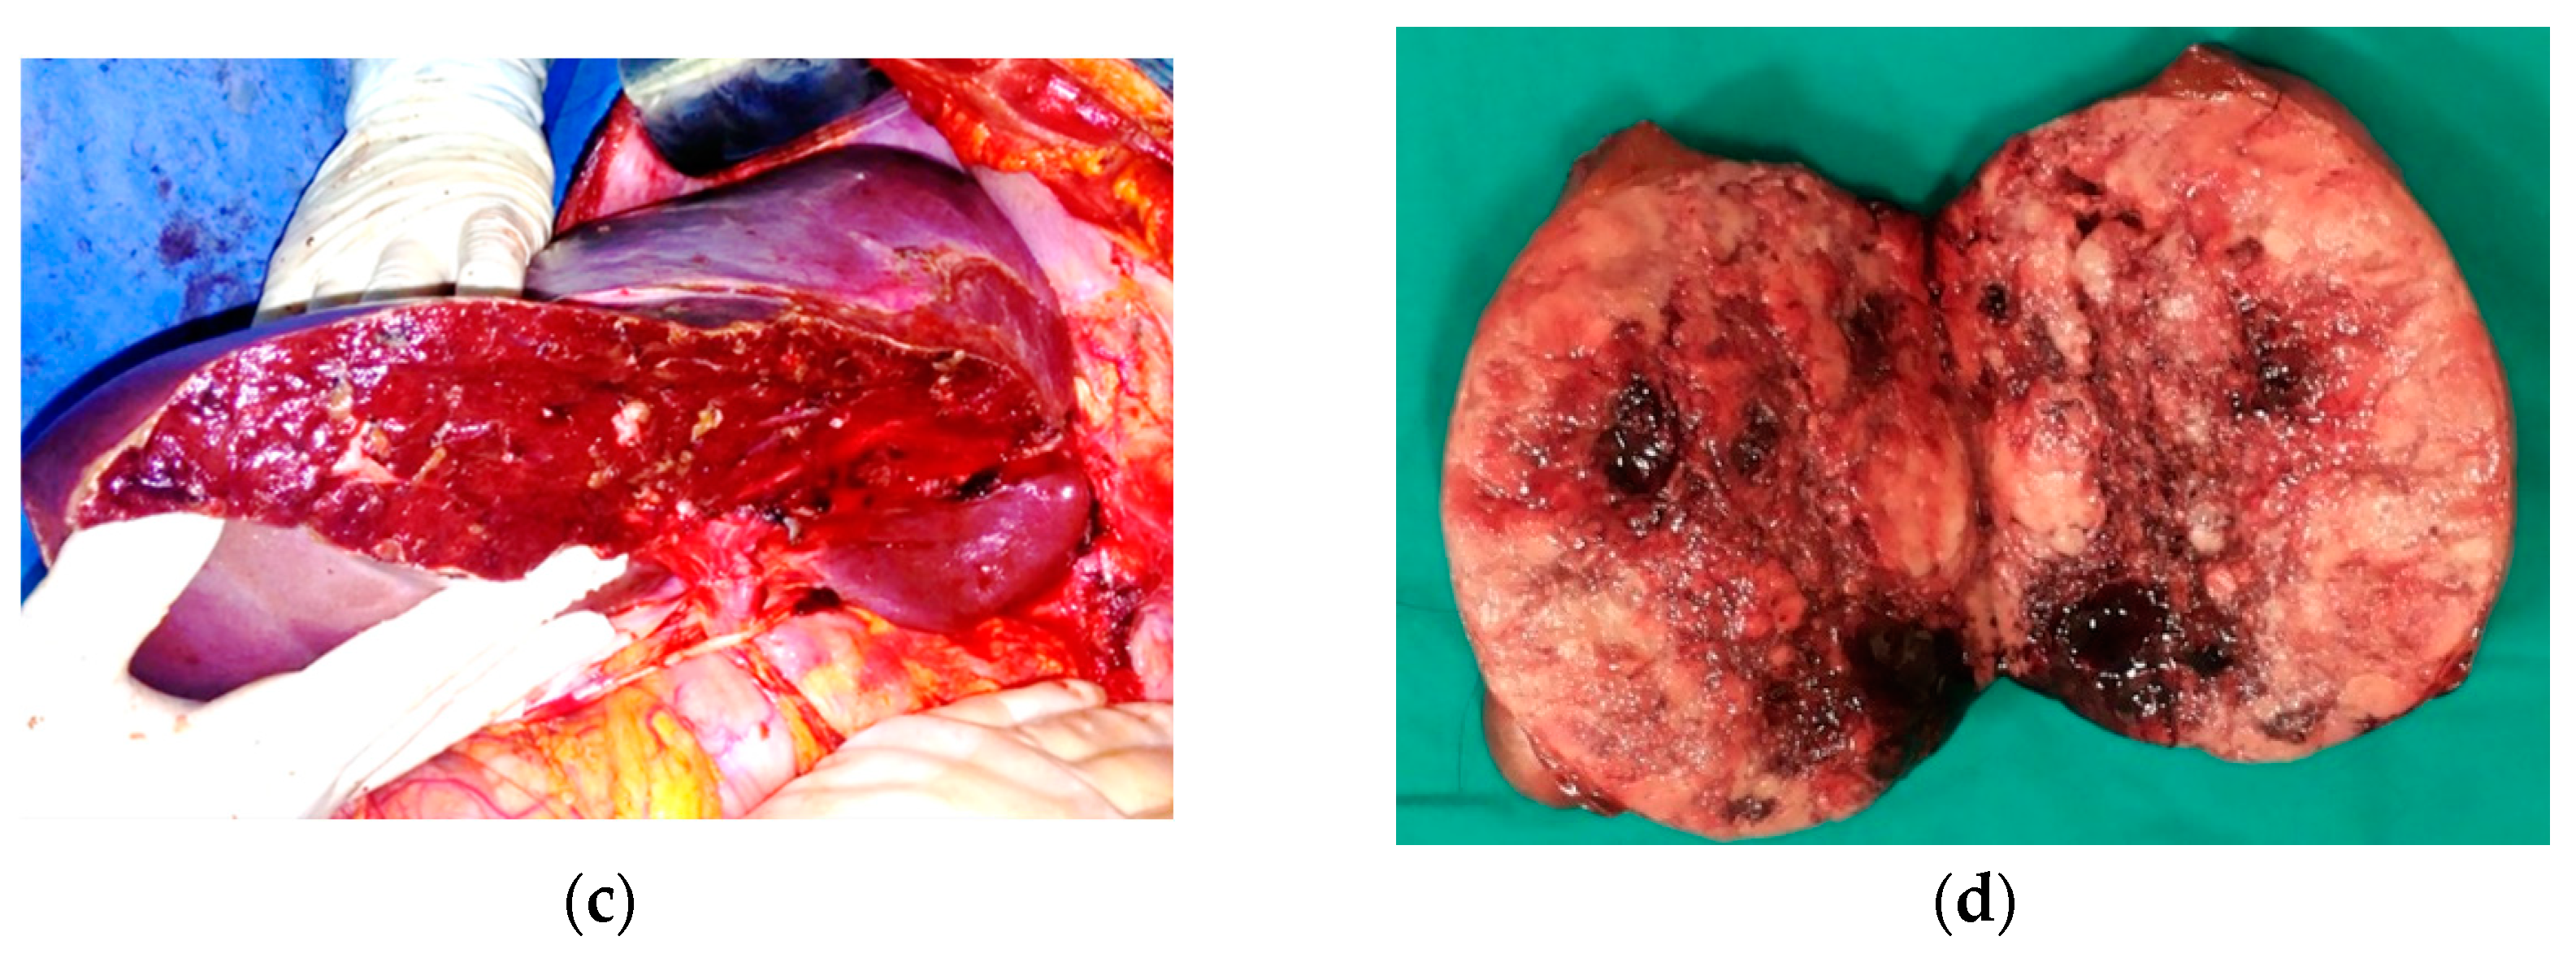

Seven weeks after the first resection, we performed the second stage of the debulking procedure, which consisted of an intraoperative ultrasound-guided right posterior sectionectomy extended to segments 5 and 8, along with the resection of the invaded right hepatic vein, removing the large confluenced metastases located in the right hemiliver (Figure 6) with a portocaval shunt using Gore-Tex graft interposition to decrease post-resectional portal hypertension.

Figure 6.

Second-stage surgery. Aspect of the liver: (a) prior to second resection; (b) after resection; (c,d) resected specimen.